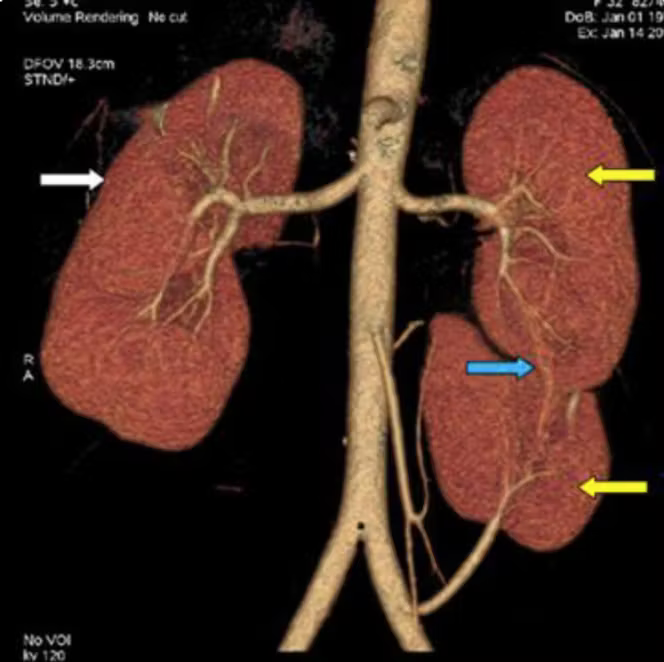

C’est l’histoire d’un homme de 63 ans qui consulte aux urgences pour une douleur lombaire gauche persistante. L’examen clinique et les analyses sanguines sont normaux. Rien, à première vue, ne laisse présager une anomalie anatomique. Et pourtant, l’échographie abdominale met en évidence une configuration inattendue : non pas deux reins, mais trois, dont deux sont fusionnés en une structure en fer à cheval.

Le scanner confirme la présence de trois reins distincts : deux reins fusionnés dans la fosse rénale gauche et un troisième rein en position médiane, chacun doté d’une vascularisation indépendante. La fonction rénale est globalement normale. Quelques petits calculs, non obstructifs, sont observés dans les reins gauches.

Ce cas, rapporté en mars 2026 dans la revue Radiology Case Reports par des radiologues marocains de l’hôpital Ibn Sina à Rabat, associe deux anomalies congénitales déjà rares en elles-mêmes (rein surnuméraire et rein en fer à cheval), aboutissant à une configuration d’une exceptionnelle rareté.